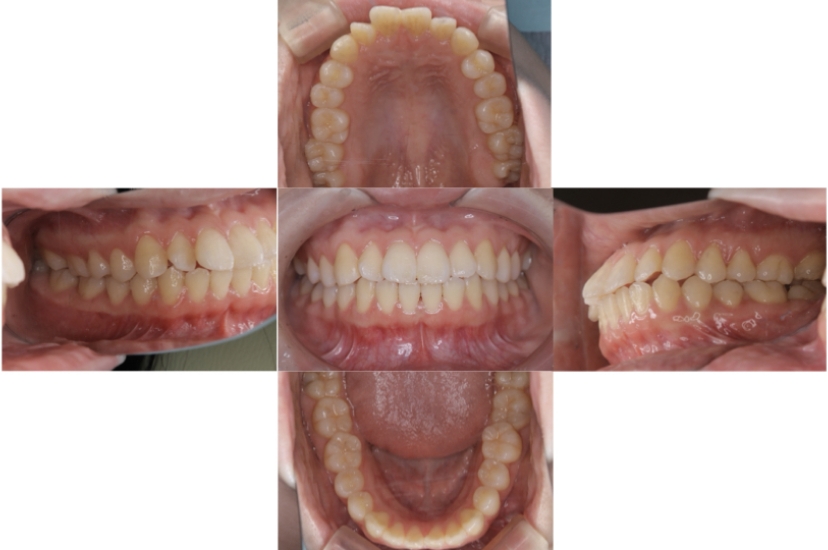

上下顎叢生、反対咬合(上下の前歯のガタガタ、若干受け口)のケースです。

装置はラビアル(上下表側)で、上下顎の小臼歯を4本抜歯を行っています。抜歯したスペースを使って、上下の叢生改善と前歯の受け口の改善を行っています。

主訴 前歯のガタガタを治したい。

年齢・性別 45歳 女性

お住まいの地域 神奈川県川崎市

治療方針 抜歯スペースを利用して上前歯の叢生(ガタガタ)の改善と受け口の改善

抜歯部位 上顎左右第一小臼歯、下顎左右第二小臼歯

使用装置 ラビアル(上下表側)、顎間ゴム

治療期間 2年6か月

治療回数 20回

BEFORE

AFTER